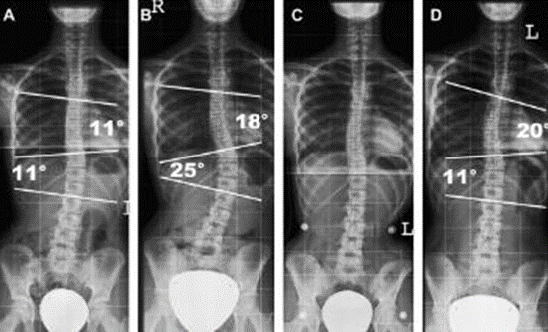

Scoliosis Studies

Scoliosis is defined as a lateral spinal curvature. Images of the entire spine is analysed for the degree of scoliosis and are measured for the purpose of correction.